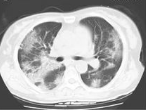

正常肺

ARDS患者肺